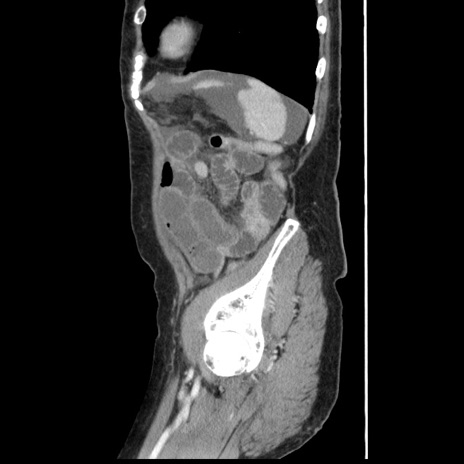

横断像

【症例】80歳代女性

【主訴】腹痛

【現病歴】8時間前から腹痛あり来院。

【既往歴】糖尿病、脂質異常症、子宮体癌にて子宮全摘術

【身体所見】意識清明・会話良好だが腹痛で苦悶様、全腹部にわたって反跳痛と圧痛あり

【データ】WBC 13600、CRP 0.14、LDH 224、CK 90